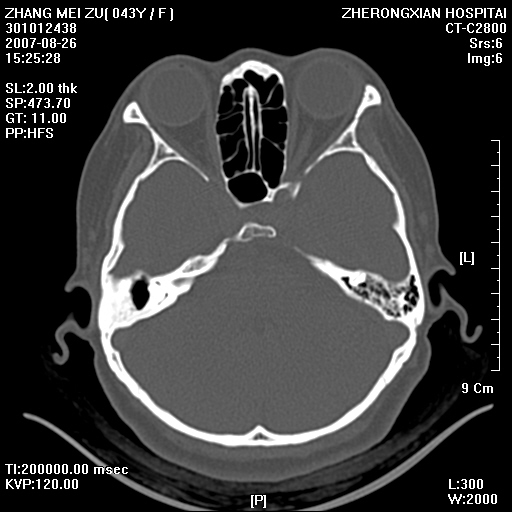

标题: CT9512:F43Y,是肉芽肿还是胆脂瘤?诊断报告该如何出? [打印本页]

标题: CT9512:F43Y,是肉芽肿还是胆脂瘤?诊断报告该如何出?

右耳硬化性乳突炎并鼓窦入口胆脂瘤形成,左侧乳突炎

右侧中耳乳突炎,伴鼓窦入口胆脂瘤形成.

右侧硬化型乳突。

胆脂瘤形成。

支持右侧中耳乳突炎伴鼓窦入口处胆脂瘤。

典型胆脂瘤,从上鼓室,乳突窦入口到乳突窦有明显光滑的骨质破坏和软组织结节均为胆脂瘤特点.而肉芽肿对骨质的破坏是轻微的.值得关注的是乳突后壁被破坏只剩薄薄的一层,如果再不尽快治疗,胆脂瘤如果突破其后壁即可能形成耳源性脑脓肿了.